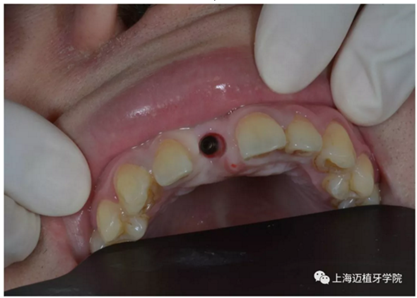

3月后恢復良好,上愈合基臺

2周后袖口成形

戴牙前口內(nèi)照片:

去除愈合基臺: